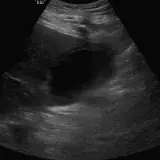

Over 2,100 interactive radiology cases, curated by radiologists for your level of training. Scroll, window, and view cases full screen — just like on PACS. Click linked findings in each writeup to jump straight to them on the image. Cases include sample reports, a focused discussion section, original illustrations, and videos.

完全交互式病例,配备您在 PACS 上期待的各项工具——滚动、调窗、缩放、平移、测量、ROI 和全屏模式。

丰富的标注直接在病例图像上突出关键发现。点击病例讲解中的关联发现,即可跳转至其在扫描上的精确位置。

像在工作站 PAC 上一样滚动、平移、调窗和缩放